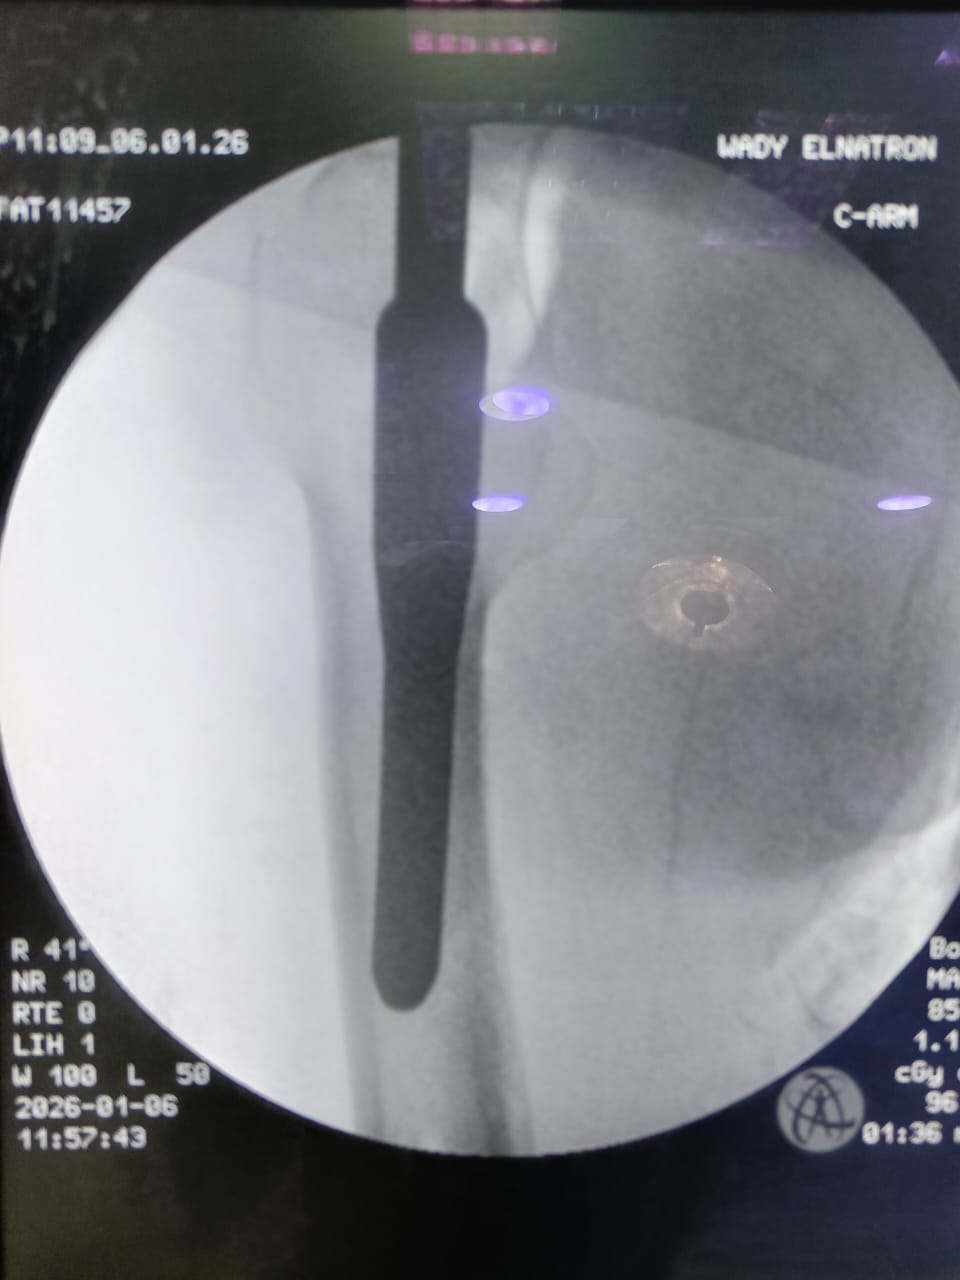

وعقب استقبال الحالة، تم إجراء التقييم الإكلينيكي الشامل والفحوصات الطبية اللازمة، وعلى ضوء النتائج تقرر التدخل الجراحي العاجل، حيث تم إجراء رد مغلق وتثبيت لكسر أعلى الفخذ الأيمن بين المدورين باستخدام مسمار نخاعي تشابكي (جاما نيل) المخصص لمثل هذه الكسور، بما يحقق ثباتًا جيدًا للكسر، ويساهم في سرعة التعافي وتقليل فرص حدوث المضاعفات.